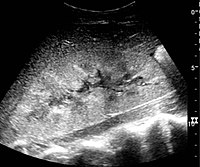

Bacterial inflammatory disease of the kidney is commonly cause Eschericia coli. Most infections begin as UTI that ascends to the upper genitourinary system. the infection spreads from the renal pyramids into the renal cortex. The infection may be focal or diffuse. This condition usually presents with chills, fever, flank pain and laboratory findings of urinary infection.

Ultrasound may show an enlarged kidney with edema and increased echogenicity. You may also see a focal triangular area of altered echogenicity that displays reduced perfusion with color Doppler and power Doppler. If left untreated or inadequately treated that area can turn into an abscess.

An abscess will be well formed and distinct from the remainder of the renal parenchyma, it will be heterogeneous, complex appearance with mixed echoic and anechoic portions and no color doppler signal internally..